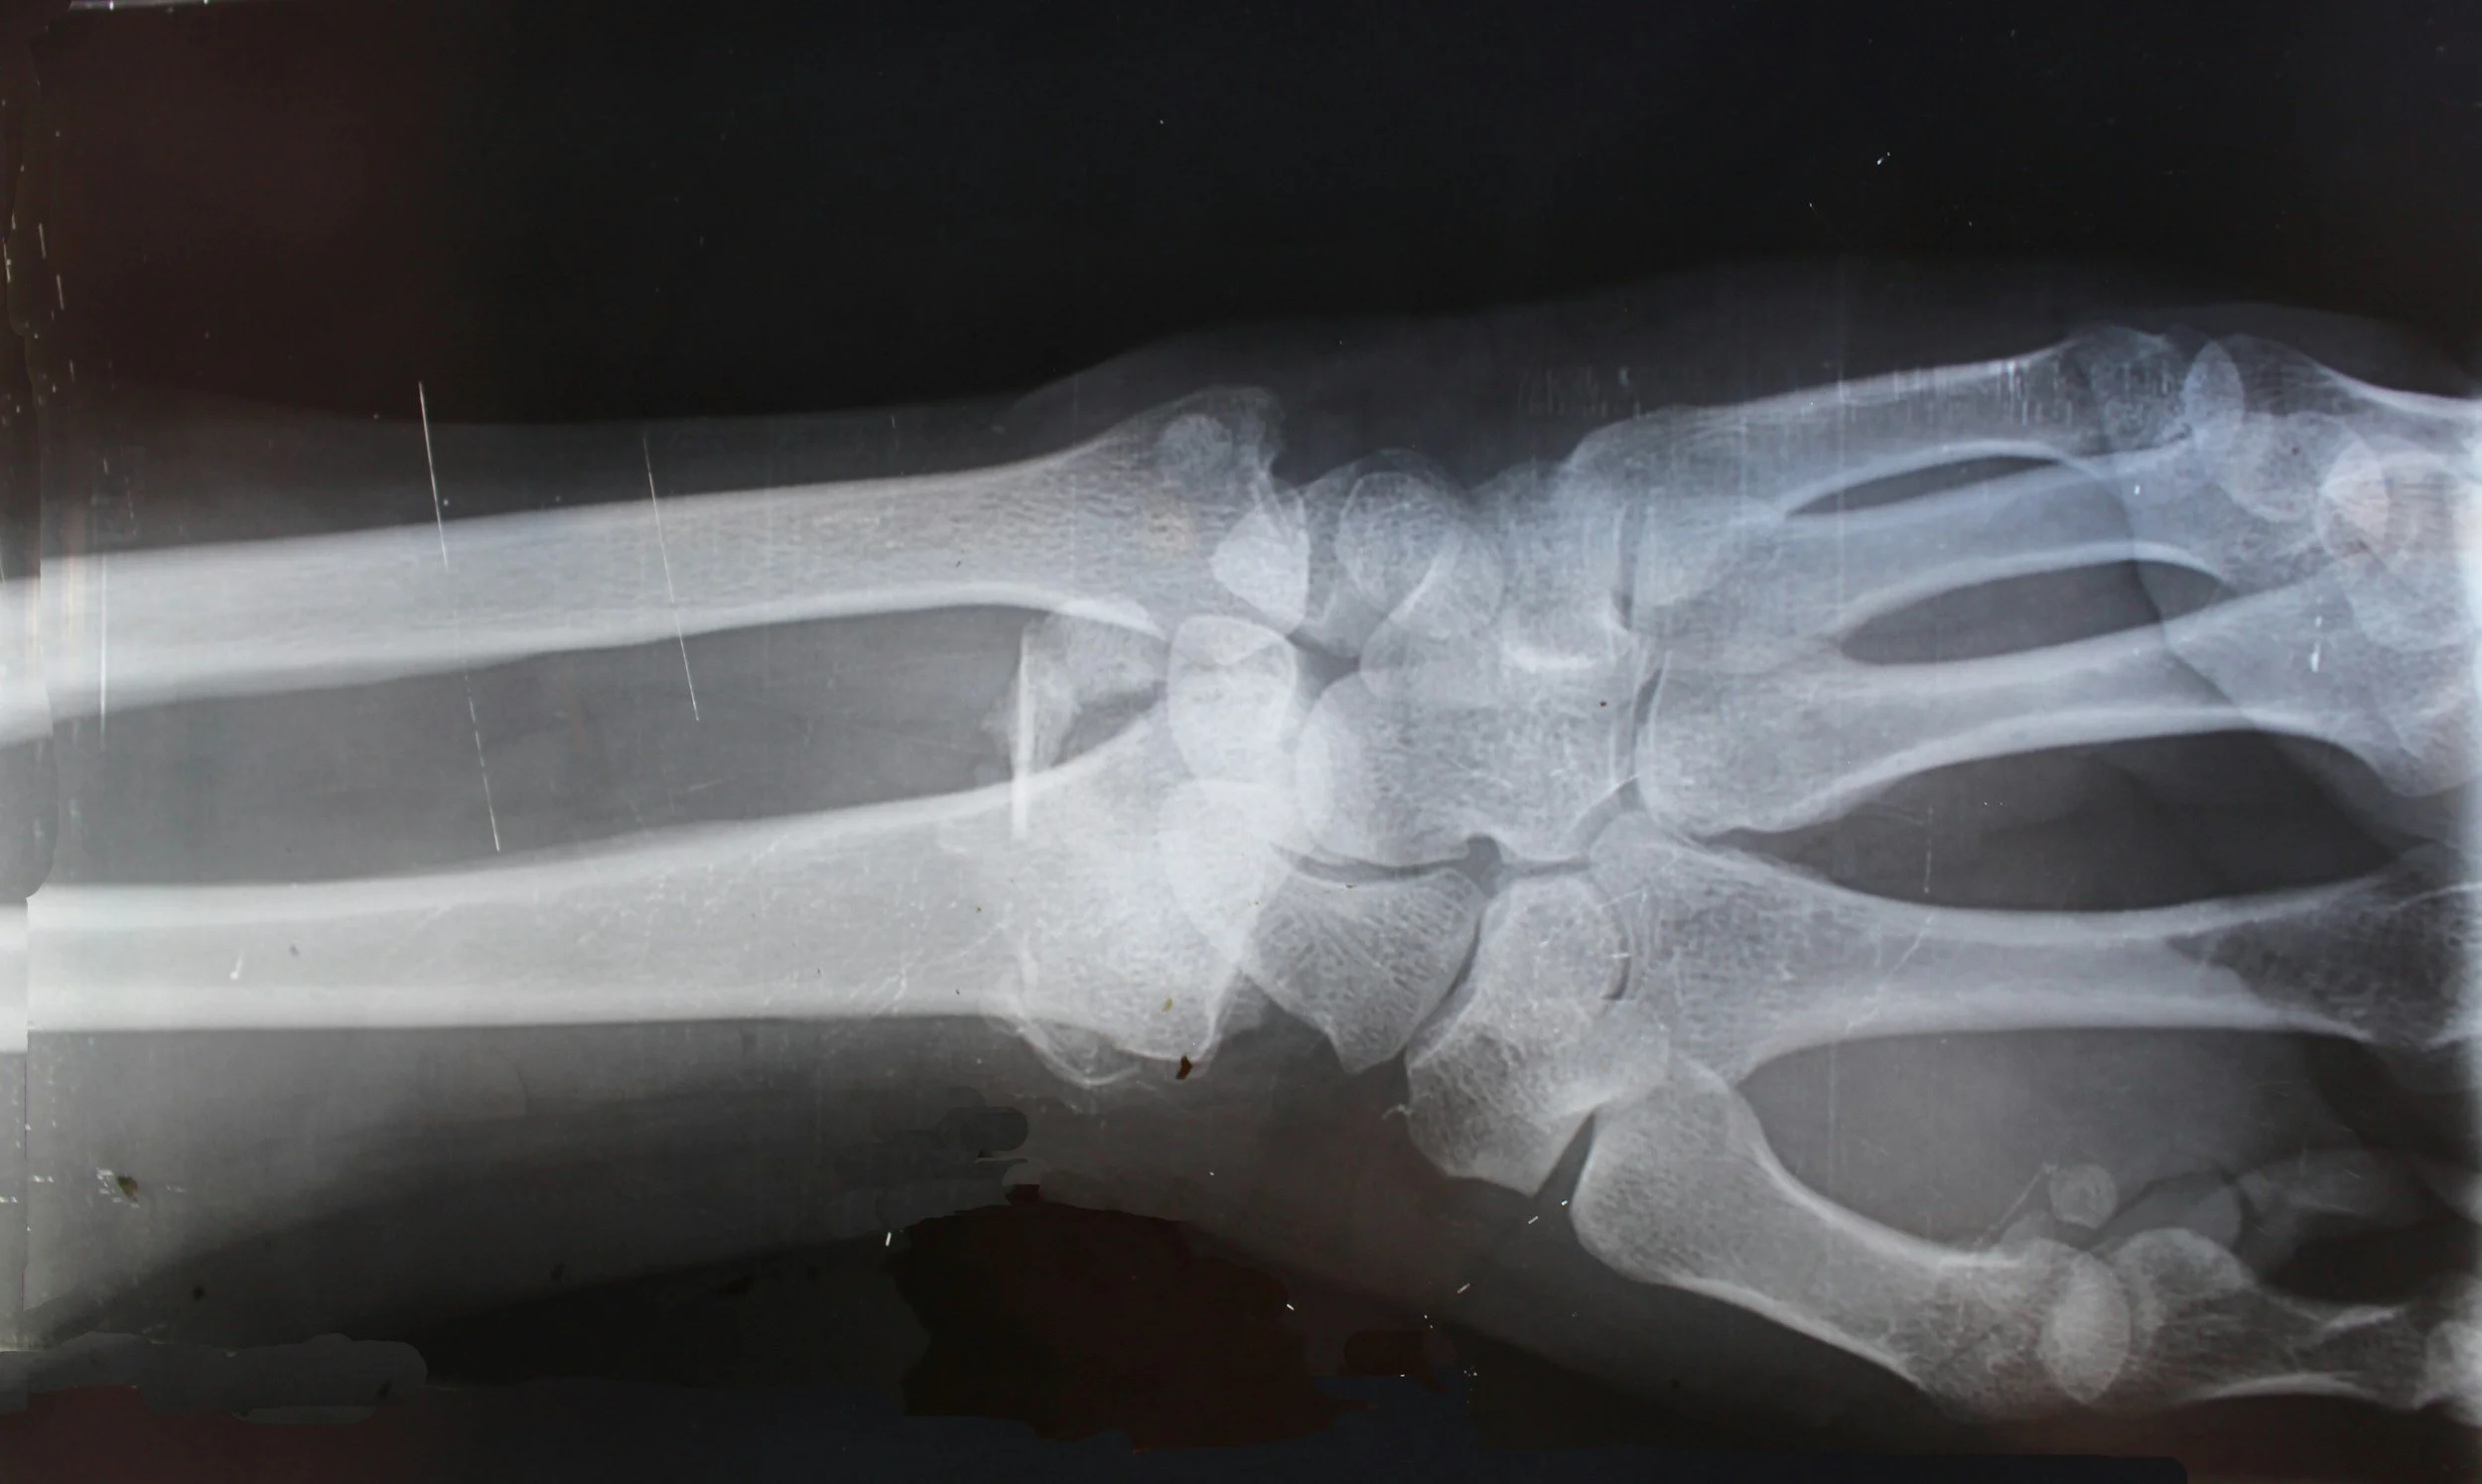

Bone Health: Beyond the DXA Scan

Bone health is about more than a DXA scan and a prescription. Learn what really matters for building strength and supporting long-term bone health in midlife.